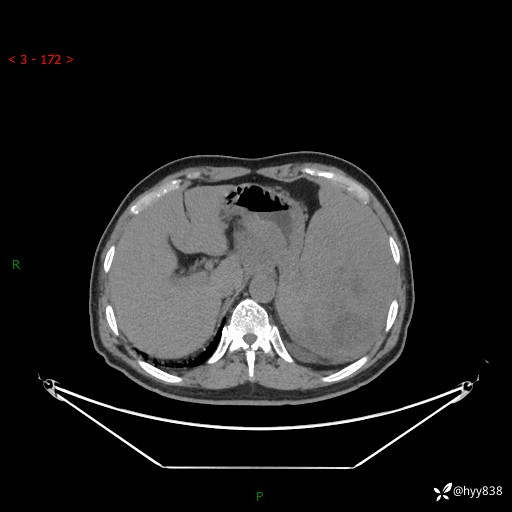

上腹部CT平扫

增强(动脉期+静脉期)